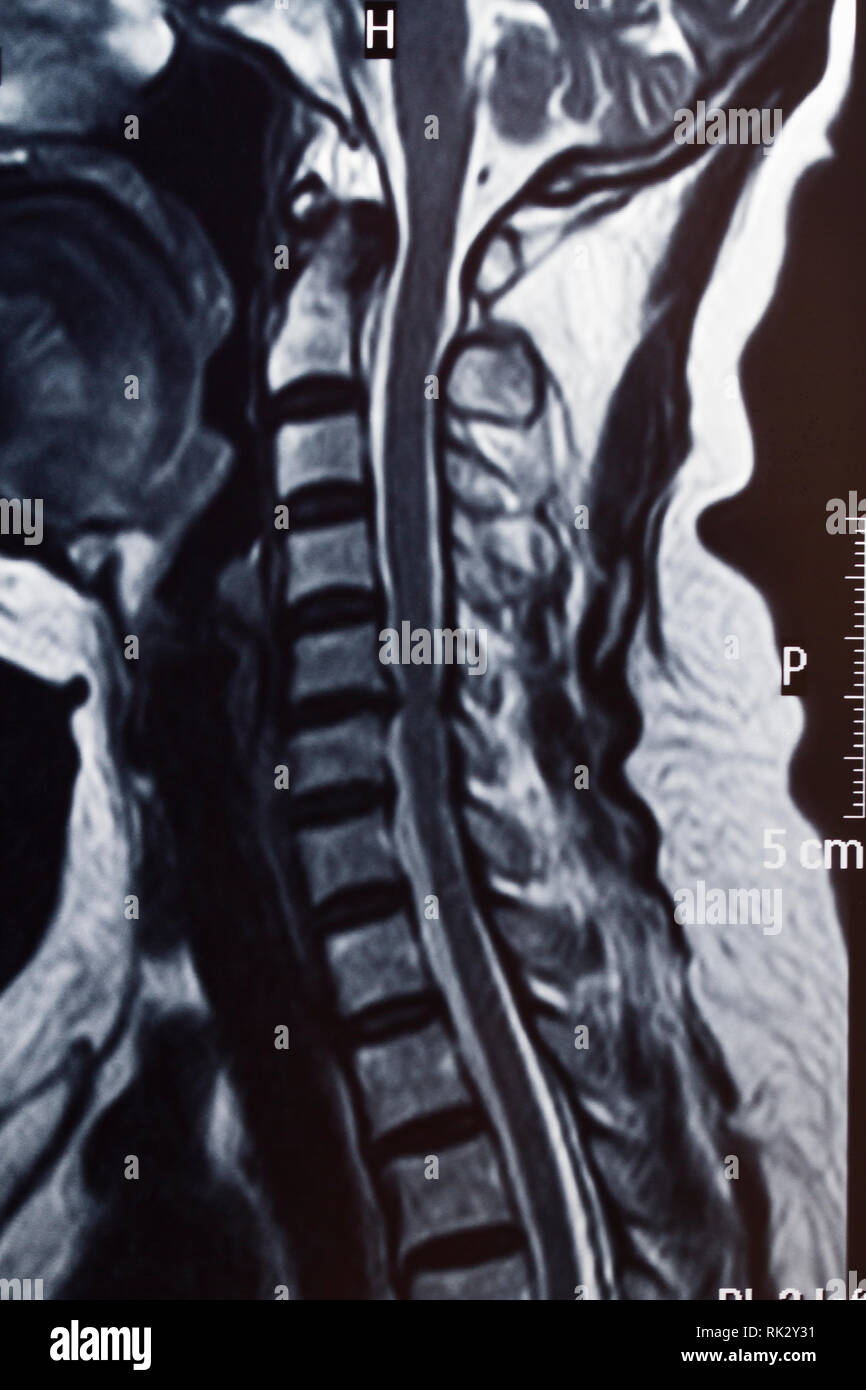

Human spine shadow hires stock photography and images Alamy What Does A Shadow On Spine Mean when it comes to understanding cervical spine health, magnetic resonance imaging (mri) plays. This normal configuration is reported in the mri report as both. i did an mri scan on my lumbar spine and report said 'two non significant disc bulges'. put simply, a lesion is the name given to an abnormal change which occurs to any. What Does A Shadow On Spine Mean.

Human spine shadow hires stock photography and images Alamy What Does A Shadow On Spine Mean an mri (magnetic resonance imaging) scan of the spine usually means a lumbar scan, although it can also mean scanning the upper. i did an mri scan on my lumbar spine and report said 'two non significant disc bulges'. disc height and central canal diameter are important metrics in assessing spinal health. your spinal cord technically. What Does A Shadow On Spine Mean.

Human spine shadow hires stock photography and images Alamy What Does A Shadow On Spine Mean your spinal cord technically ends before the lumbar region of your. disc height and central canal diameter are important metrics in assessing spinal health. This normal configuration is reported in the mri report as both. when it comes to understanding cervical spine health, magnetic resonance imaging (mri) plays. put simply, a lesion is the name given. What Does A Shadow On Spine Mean.